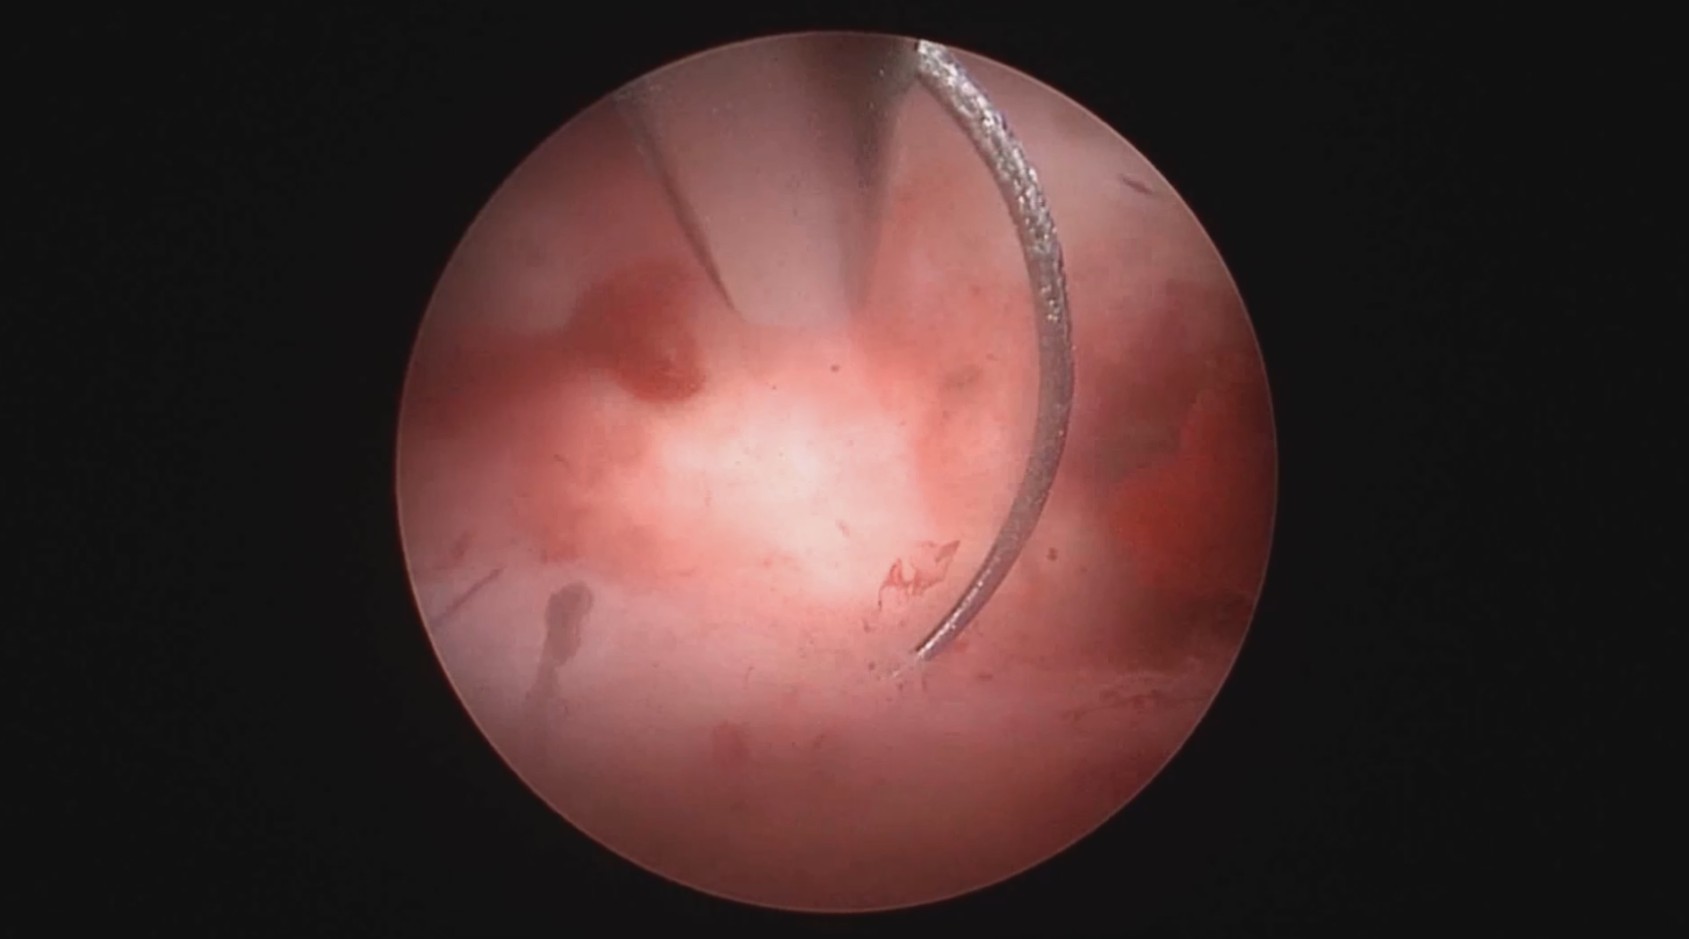

患者39岁,G4P2,顺产2次。2025年2月因异常子宫出血,阴道出血淋漓不净1+月行宫腔镜检查及内膜活检,病检为子宫内膜增生(无非典型)伴息肉形成。2025年3月,行经第3天,月经量大伴腹痛,要求放置曼月乐并固定。宫腔镜见内膜杂乱,脱落不全,吸刮内膜送病检,4-0不可吸收线将曼月乐环缝合固定于宫腔上段后壁。术中打结、推结很困难,放弃打结,留较长线尾在宫颈管,必要时可牵拉线尾调整节育环位置,只要缝合到子宫肌层,肌肉的卡压阻力可以起到固定作用,继续探索不用打结推结的固定方法。术后多次复查B超,子宫偏大,7.7cm*6.6cm*7.8cm,环顶端距宫底3cm。